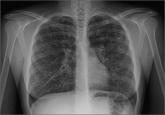

ArticleHelping patients with cystic fibrosis live longerAuthor:Douglas Lewis, MD, FAAFPPublish date: March 1, 2016 Lung and pancreas dysfunction are just part of the CF picture. Managing this “full-body disease” requires timely testing, traditional ...Read More